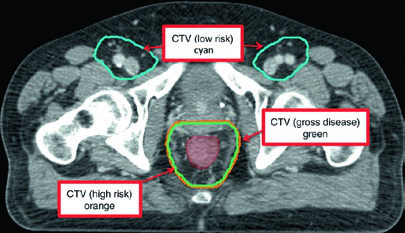

| GTV-P, GTV-N | GTV-P: all gross disease on physical examination and imaging. GTV-N: nodes ≥1.5 cm, PET-positive, and/or biopsy-proven. Distinguish GTV-Na (≤3 cm) from GTV-Nb (>3 cm) |

| CTV-P, CTV-N | CTV-P: GTV-P + 1.5–2.5 cm margin excluding uninvolved bone, muscle, or air. CTV-N: GTV-N + 1.0–1.5 cm excluding uninvolved bone, muscle, or air |

| CTV-HR (high risk) | Covers CTV-P, CTV-N, entire mesorectum, perirectal nodes, and bilateral internal iliac nodes inferior to the inferior border of the sacroiliac joint. If inguinal or external iliac nodes are involved, include these regions. 0.7 cm margin around internal iliac vessels. 1.8 cm strip between external and internal iliac vessels for obturator nodes. 1–1.5 cm anteriorly into bladder |

| CTV-LR (low risk) | Covers uninvolved internal iliac nodes superior to the sacroiliac joint inferior border, plus uninvolved external iliac and inguinal nodes. Margins: 0.7 cm around internal iliac vessels; 1 cm anterolateral on external iliacs; entire inguinal compartment contoured |

| PTV | 0.5–1 cm expansion from each CTV, depending on setup accuracy, imaging frequency, and IGRT use |